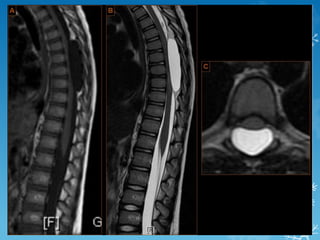

4th ventricle ependymoma